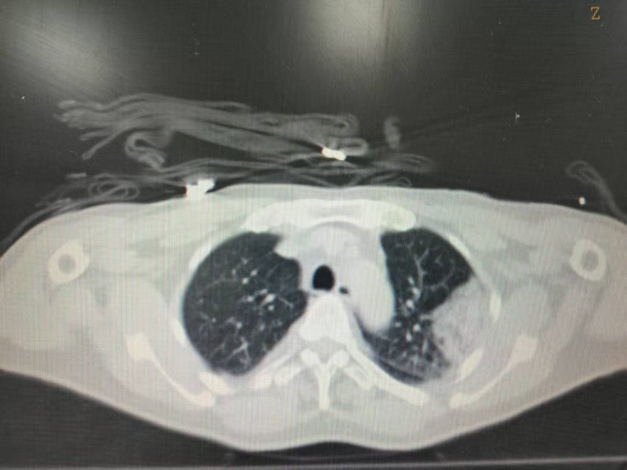

术后即刻CT平扫,冷冻范围超过病灶边界5mm

患者为中年男性,曾接受肾盂癌根治手术,术后因肿瘤复发开始免疫治疗。治疗期间,患者肺部出现孤立性转移病灶缓慢增大(寡进展)。经多学科讨论,肿瘤内科决定采用冷热多模态消融技术对肺部转移病灶进行处理。术中根据规划路径,在CT引导下将消融针经皮穿刺至病灶位置;行2个冻融循环,复查消融范围超出病灶边界5mm;复温状态下逐步拔出穿刺针。整个手术耗时约1小时,术中患者无疼痛刺激及咯血,术后无气胸。术后第二天顺利出院。